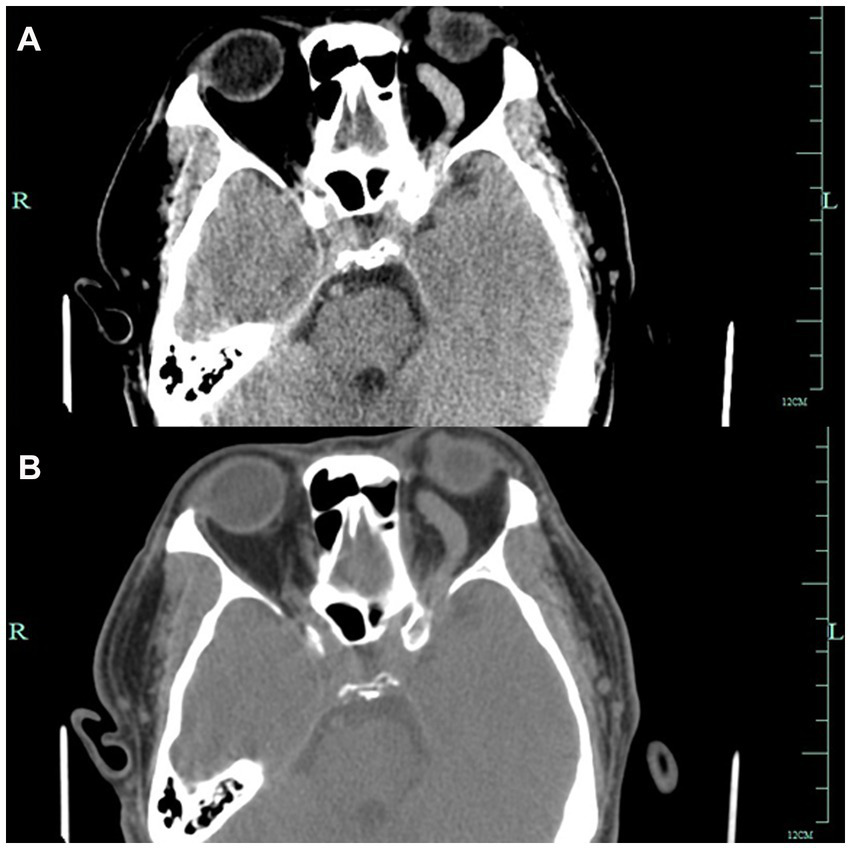

A 52-year-old man presented to the ophthalmology department with a 3-month history of left eye redness and proptosis (Figure 1A). The patient reported no history of trauma or systemic diseases. Ophthalmic examination revealed significant tortuosity and dilation of conjunctival veins, particularly prominent in the nasal area (Figures 1C,E). Mild left eye proptosis was noted, but visual acuity and ocular motility were relatively intact. Intraocular pressure was within normal limits. Given the clinical findings, a cranial computed tomography was performed, which suggested a suspected a left carotid cavernous sinus fistula (Figures 2A,B). The patient was subsequently referred to the neurosurgery department for further management.

Figure 2

Figures A and B show Axial CT images showing left-sided proptosis with thickening of the sclera. The left optic foramen is enlarged, and the left cavernous sinus exhibits heterogeneous density. The left superior orbital vessels appear tortuous and dilated.